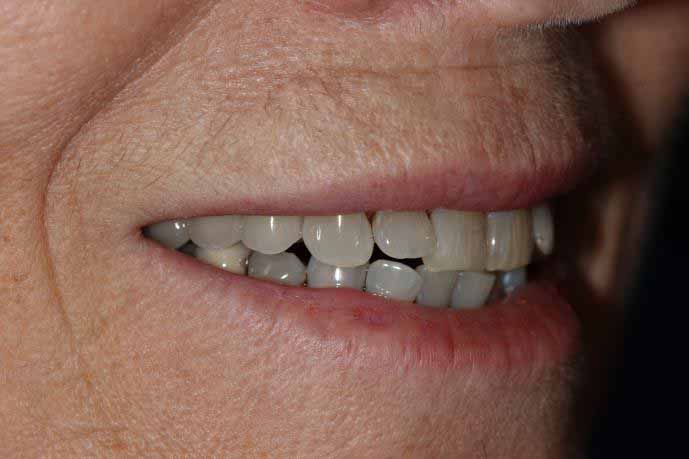

Upper Front Tooth Implant

Both upper front teeth were in a bad way, the upper left one had to be removed as was beyond repair, this was replaced with an implant and a temporary crown on the same day; the upper right front tooth was repaired with a crown. Photos show the result with the definitive crowns after 3 months of treatment.